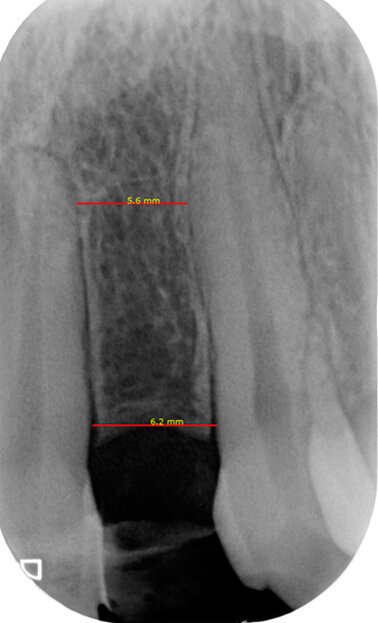

Fig. 4a - Rx endorale pre-operatoria sito edentulo sede 22. Misurazione dello spazio inter-radicolare per l’inserimento dell’impianto.

Prima dell’inizio dei lavori implanto-protesici e al termine del trattamento ortodontico della durata di circa un anno, è stato eseguito un condizionamento di tessuti molli nel sito edentulo tramite rifacimento della protesi tipo Maryland in sede 22. Utilizzando le sezioni CBCT e le ricostruzioni 3D è stata poi eseguita la progettazione virtuale del caso, simulando il posizionamento dell’impianto nel sito preparato ortodonticamente il cui alloggiamento ottimale è stato individuato come al centro del futuro elemento protesico13. Dopo l’esecuzione di un lembo di accesso a tutto spessore, si è proceduto alla preparazione del sito implantare. È stata eseguita una procedura di rigenerazione ossea in sede 22 con Bio-Oss 0.5 e Bio-Gide 25 x 25; è stato poi posizionato un impianto di 13 mm e diametro 3 mm, con particolare attenzione alla tridimensionalità mesio-distale, vestibolo-palatale e apico-coronale (Figg. 4a, 4b). A sette mesi dalla prima fase chirurgica è stata effettuata la seconda fase chirurgica per il posizionamento della vite di guarigione.